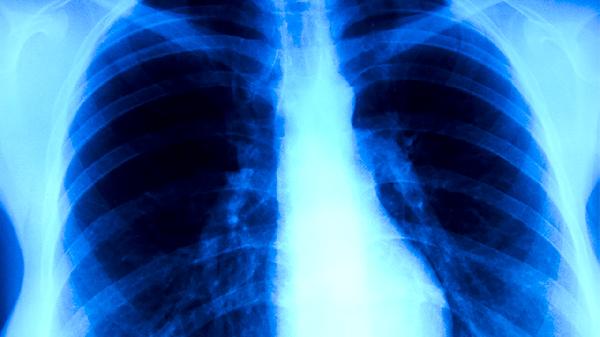

手术前需评估患者心肺储备能力,通过肺功能检查、心脏彩超等明确耐受性。若第一秒用力呼气容积占预计值百分比FEV1%>60%,通常可耐受肺叶切除;合并中重度慢性阻塞性肺疾病或心力衰竭者需谨慎。

周围型肺癌如肺段或肺叶病灶更适合手术,中央型肺癌可能需评估支气管成形术可行性。肿瘤直径小于3厘米且未侵犯胸膜的IA期患者,术后5年生存率可达70%以上。